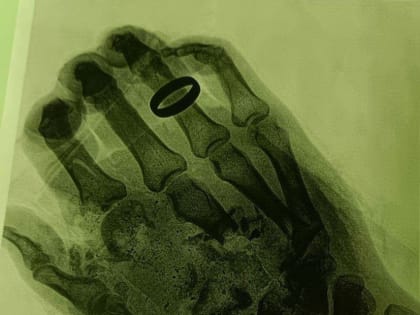

В Орехово-Зуеве врачи восстановили человеку кисть, которая была раздроблена взрывом газового баллона

Пострадавшего 36-летнего мужчину доставили в местное медучреждение с размозжением мягких тканей кисти правой руки и